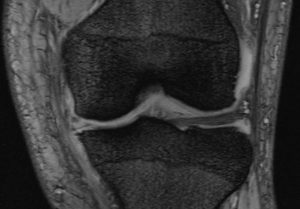

7月4日の朝、会社に向かって歩いていたら足がおかしくなってきたのです。それも急に。足がもつれ、膝が曲がらなくなるのでした。ふだん10分で来るところをもつれてしまい30-40分かかる状態でこれはまずいと整形外科へ。するとレントゲンを撮って診察ですが、先生より変形性膝関節症という病名を告げられヒアルロン酸打ちますか?と一言。

WEB予約してMRIを取ってくるように言われ、銀座にあるこのクリニックに行って診察すると幹脂肪だかなんだかの注射とやらと説明を聞いていましたが最後に値段を聞いて腰抜かしました。